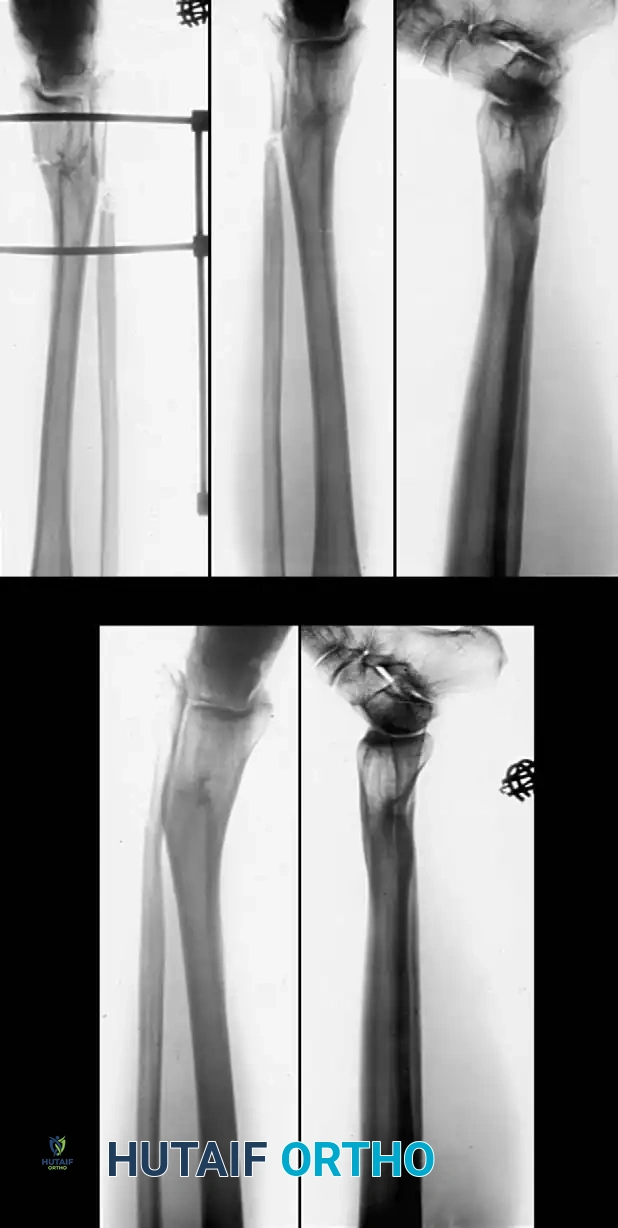

Fig. 6: (A, B) Varus malunion of the distal tibia. (C) Osteotomy of the tibia and fibula with reduction maintained by a circular external fixator. (D, E) Tibial union obtained with normal alignment.

Fig. 3: Supramalleolar dome osteotomy. (A) Dome osteotomy created 1 to 1.5 cm proximal to the ankle joint. Threaded pins are inserted parallel to the ankle and knee joint lines. (B) Osteotomy completed, and pins brought parallel to correct varus or valgus deformity.

- Fixation: Stabilize the osteotomy. If using an external fixator, apply it in standard fashion with pins traversing the tibia and the talus. Alternatively, internal fixation with a contoured plate and screws can be utilized if the soft tissue permits.